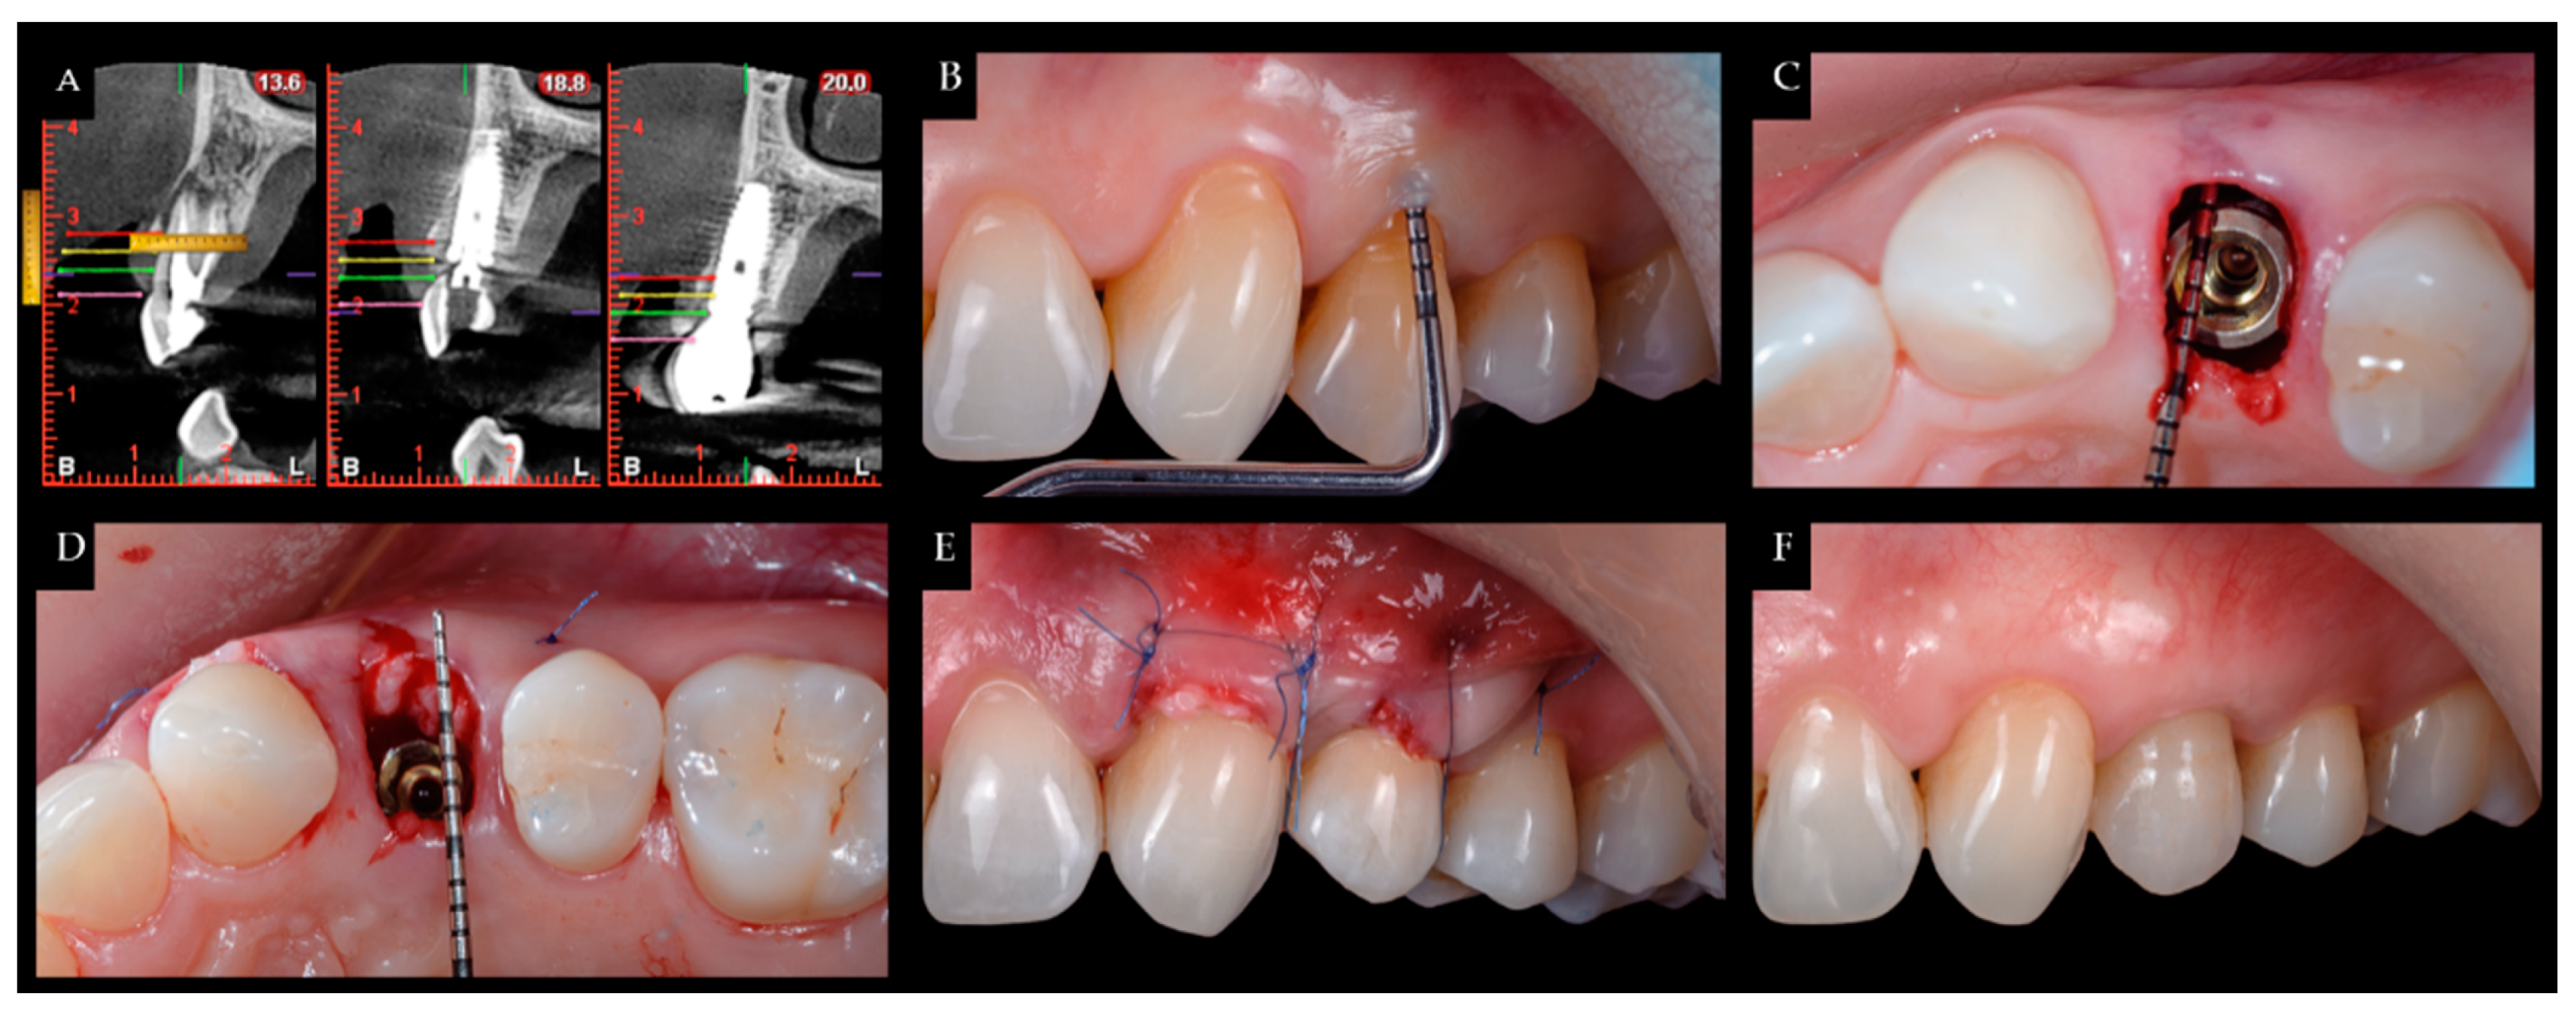

During surgery and implant placement, a connective tissue graft was harvested, and/or a socket shield technique was carried out. Both techniques are described below. The bone crest dimensions were analyzed with a periodontal probe during surgery. Based on previous publications, the changes in peri-implant tissues volume were measured using a CBCT radiological study (Planmeca Promax 3D, Helsinki, Finland) immediately after implant placement and at check-ups by a single well-trained examiner (R Gómez-Meda) to ensure measurement consistency [21]. CBCT images were undertaken based on the radiological images of the Planmeca viewer software (Planmeca Romexis v. 3.8.3.R, Helsinki, Finland) (Figure 1 and Figure 2). The study was undertaken in Meda Dental Clinic (Ponferrada, Leon, Spain).

Figure 1. (A) CBCT measurement of the gingival margin (pink line), and marks at 3, 5, and 7 mm (green, yellow, and red lines, respectively); (B) crestal height location; (C) distance from the bone crest to the implant platform; (D) tunneling of a connective tissue graft; (E) suture; (F) one-year postoperative.